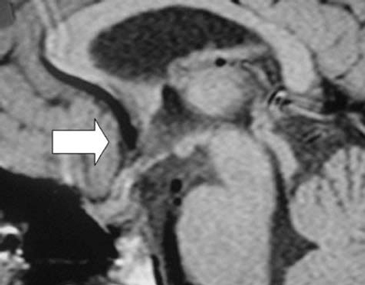

Posterior a la cirugía, se mantiene con tratamiento hormonal de reemplazo con normalización de los niveles de T4 (7,3 ug/dL) y cortisol (12,7 ug/dL). La medición de anticuerpos antihipofisiarios, antitiroideos y antiadrenales resultó negativa. Una nueva RNM al séptimo mes de la cirugía, mostró desaparición completa de la masa descrita. (Figura 3 y Figura 4). En estas imágenes se observa una glándula hipófisis de tamaño y morfología normales, con intensidad de señal homogénea. En los cortes sagitales se aprecia tenuemente la hiperintensidad de la señal neurohipofisiaria y no se reconocen lesiones satélites.